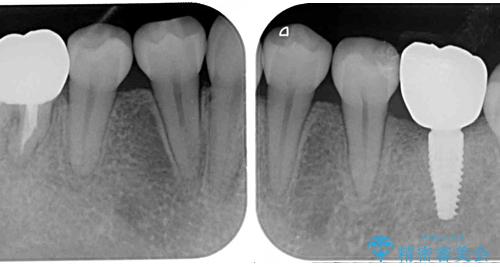

矯正治療を行う前に、根管治療の必要な上顎前歯と下顎大臼歯の根管治療を行い、矯正治療の途中で下顎の欠損部にインプラント埋入することとし、矯正治療後に補綴治療を行うこととしました。

矯正治療中にインプラント埋入を行うなど、余計な時間や無駄のない治療を行うことができました。